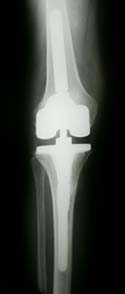

Knee joint implants

Your doctor can recommend knee replacement surgery if you are suffering from severe knee pain or your mobility is limited because of rheumatoid arthritis, degenerative joint disease or injury. Knee replacement surgery will relieve your pain and allow you to live a full life.

During the operation the orthopaedic surgeon will replace your damaged joint with an artificial implant.  A complete knee joint replacement is the most common procedure. However, some patients can benefit from a partial knee joint replacement.

Implants are made from metal alloys, ceramic materials or artificial materials and they are attached to the bones with the use of acrylic cements. There are different kinds of implants. Your surgeon will talk to you about the kind of implant that meets your needs.

Elements of the knee joint prosthesis

Up to three bone surfaces may be replaced in complete knee replacement surgery:

• The lower end of the femur. The metal femoral component curves around the end of the femur (thighbone). It is grooved so that the kneecap can move up and down smoothly against the bone as the knee bends and straightens.

• The top surface of the tibia. The tibial component is typically a flat metal platform with a cushion of strong, durable plastic, called polyethylene. Some designs do not have the metal portion and attach the polyethylene directly to the bone. For additional stability, the metal portion of the component may have a stem that inserts into the centre of the tibia bone.

• The back surface of the patella.. The patellar component is a dome-shaped piece of polyethylene that duplicates the shape of the patella (kneecap).

Components are designed so that metal always borders with plastic, which provides for smoother movement and results in less wear of the implant.